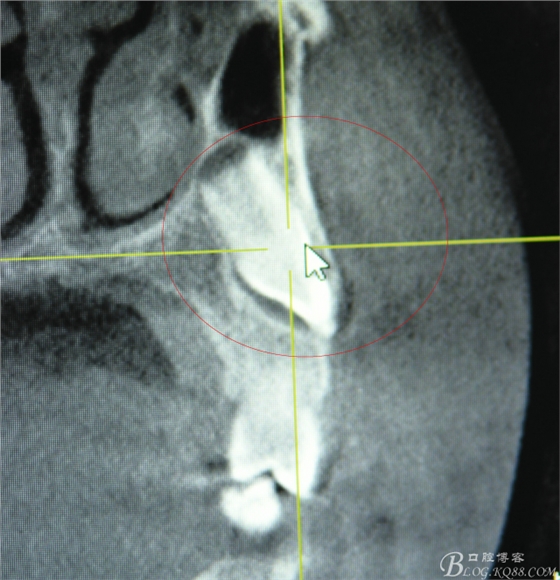

圖3.矢狀面檢查:23的唇面接近唇側(cè)骨壁、從而提示切口應(yīng)做在唇側(cè)。